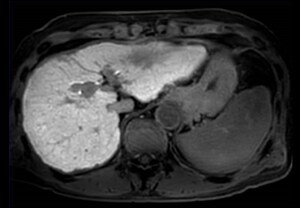

• Clinical image SmartSpeed Abdomen

SmartSpeed Abdomen comparison